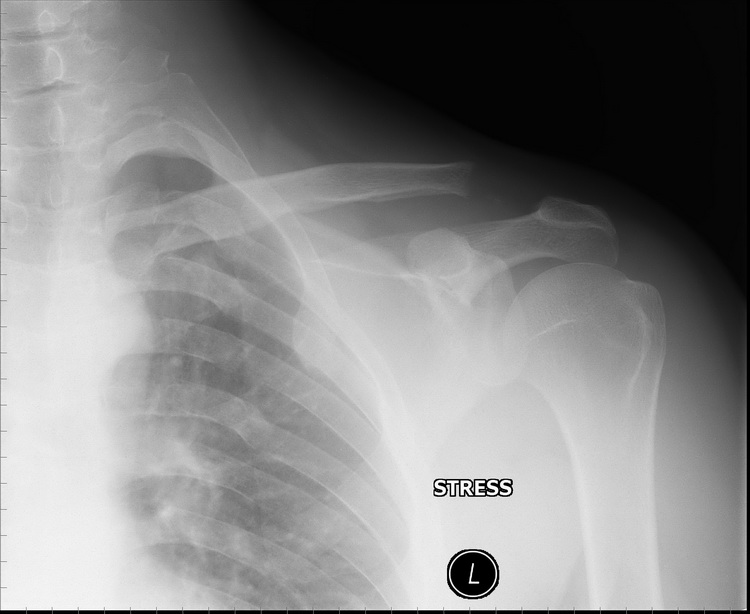

Re: Остеолиз ключицы

Еще снимки.